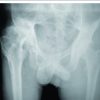

An 18-year-old male laborer fell from 10 feet height while working and sustained an injury over his right ankle. He presented to our emergency department with a grossly swollen, painful, and deformed right ankle and foot without any neurovascular deficit. The skin was intact, with ecchymoses over the dorsum of the foot. A subsequent radiograph performed after initial resuscitation demonstrated a trimalleolar fracture with a talar body fracture on the right side (Fig. 1). The fracture was initially managed with analgesics, ankle splint with limb elevation, and cold fomentation. A computed tomography scan was performed to delineate the fracture morphology, which demonstrated a comminuted talar body fracture (81B 3.3) with partial uncovering of the distal tibial articular surface and posterior migration of the posterior fragment of the talus. The posterior malleolar fragment was displaced as well as rotated concerning the tibial plafond. The medial and lateral malleolar fragments were minimally displaced (Fig. 2-4).